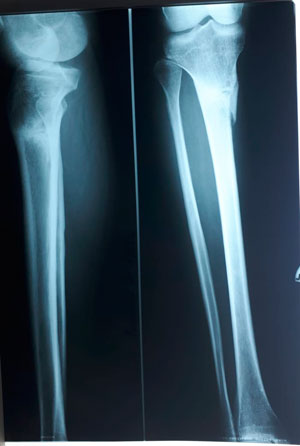

Варусная деформация голеней.

Ротация с обеих сторон.

Дата операции - 20.03.2019г.